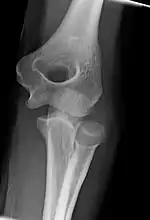

Left: Lateral X ray of a dislocated right elbow

Right: AP X ray of a dislocated right elbow

Fractures

There are three bones at the elbow joint, and any combination of these bones may be involved in a fracture of the elbow. Patients who are able to fully extend their arm at the elbow are unlikely to have a fracture (98% certainty) and an X-ray is not required as long as an olecranon fracture is ruled out.[27] Acute fractures may not be easily visible on X-ray.[28]

Dislocation

X-ray of ventral dislocation of the radial head. There is calcification of annular ligament, which can be seen as early as 2 weeks after injury.[29]

Elbow dislocations constitute 10% to 25% of all injuries to the elbow. The elbow is one of the most commonly dislocated joints in the body, with an average annual incidence of acute dislocation of 6 per 100,000 persons.[30] Among injuries to the upper extremity, dislocation of the elbow is second only to a dislocated shoulder. A full dislocation of the elbow will require expert medical attention to re-align, and recovery can take approximately 8–14 weeks.